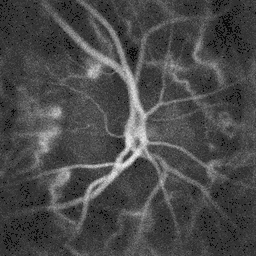

Ophthalmoscopy photograph showing the optic disc as a bright area on the right where blood vessels converge.

Blood flow in the retina and choroid in the optic disc region can be revealed non invasively by near-infrared laser Doppler imaging.[4] Laser Doppler imaging can enable mapping of the local arterial resistivity index, and the possibility to perform unambiguous identification of retinal arteries and veins on the basis of their systole-diastole variations, and reveal ocular hemodynamics in human eyes.[5] Furthermore, the Doppler spectrum asymmetry reveals the local direction of blood flow with respect to the optical axis. This directional information is overlaid on standard grayscale blood flow images to depict flow in the central artery and vein.[6]